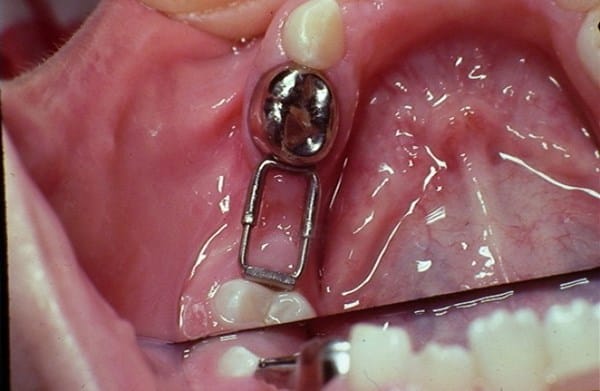

Mi hijo desde que le salieron los primeros dientes ha tenido problemas en ellos (caries, molestias).. Según los médicos por la cefalexina, ampicilina y otros que me suministraban en el embarazo y luego a el cuando nació amoxicilina.. Ha sido un martirio desde muy pequeño en el odontólogo... :'( pero lo que me preocupa comenzó hace poco mas de un año, me dijeron que tenia una caries grande en una muelita y que le debían hacer endodoncia o algo así, la cosa fue que le abrieron un hueco a la muela y le metieron un algodón con medicamento y se lo dejaron ahí como 2 meses mas o menos y el niño se quejaba constantemente pero la odontóloga decía que era normal pero le salio una bola grande en el colmillo del lado de la muela tratada la cual estaba llena de pus... Igual me seguían diciendo que no era nada grave y en la muela en esos dos meses no le hicieron revisión ni nada...

Luego este año en los primeros días de enero le volvieron a realizar lo mismo (hueco, algodón, medicamento) y lo volvieron a cerrar.. En este caso también sentía molestia y lloraba mucho, le volvió a salir la bola en el colmillo del lado pero ahora mas grande y a parte también le salio otra en la muela de atrás (la que sigue a la tratada).. Va para 4 meses con este algodón ahí dentro